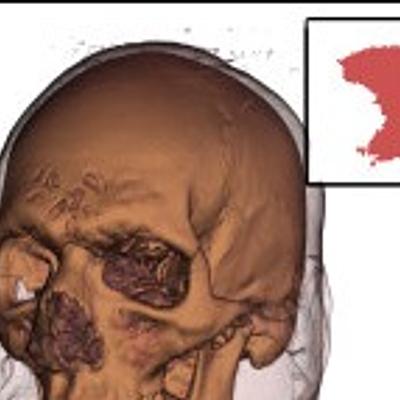

Daniel F. Malan, Stefan van der Walt, Renata Georgia Raidou, Bas van den Berg, Berend C. Stoel, et al.

International Journal of Computer Assisted Radiology and Surgery, 2016